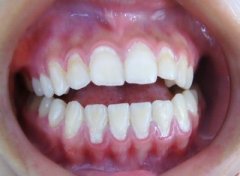

前牙开颌矫正效果怎么样?

大多数前牙开颌患者都接受矫正来治疗,前牙开颌是一种牙齿畸形,影响外貌美...【详细】